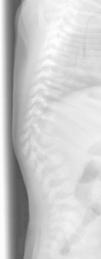

A las 24h del alta reaparece la fiebre. En la exploración física destaca protrusión en la región dorsal baja con angulación vertebral. Se realiza radiografía dorsolumbar que muestra cifoescoliosis con desaparición casi total del cuerpo vertebral de L1 compatible con espondilitis (fig. 1). Se recoge hemocultivo y se inicia cobertura antibiótica con cloxacilina y cefotaxima. Se realiza nueva RM de columna que muestra aplastamiento vertebral de L1 y cambios circundantes que sugieren espondilodiscitis con colección flemonosa de D11 a L1–L2 (fig. 2). No presenta, sin embargo, ningún hallazgo patológico en la nueva gammagrafía ósea realizada (99mTc-HMDP). Se optimiza la antibioterapia a teicoplanina y cefotaxima, que se prolonga durante dos semanas y se coloca un corsé ortopédico. Posteriormente completa 6 semanas más de tratamiento antibiótico oral con cefadroxilo a 100mg/kg/d.